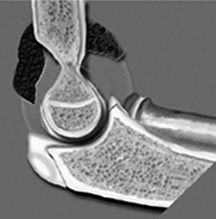

Diagram of a distended joint capsule with the fat pads displaced.

The way to evaluate joint effusion in the elbow is to look for a positive fat pad sign. Normally, when the elbow is flexed to 90°, the anterior fat pad may be seen just anterior to the joint; the posterior fat pad is not seen because it is located in the intercondylar fossa. With joint distention, the fat pads are displaced away from the joint in the anterior aspect; the fat pad will be elevated away from the joint and the posterior fat pad will be visible.

If a positive fat pad sign is not present in a child, significant intra-articular injury is considered unlikely; but on the other hand, if a visible fat pad sign is demonstrated without the appearance of a fracture, the patient should be treated as having a non-displaced fracture and should be splinted for two weeks and then re-evaluated. It is generally agreed that in the case of trauma, a displaced posterior fat pad is virtually pathognomonic of the presence of a fracture.